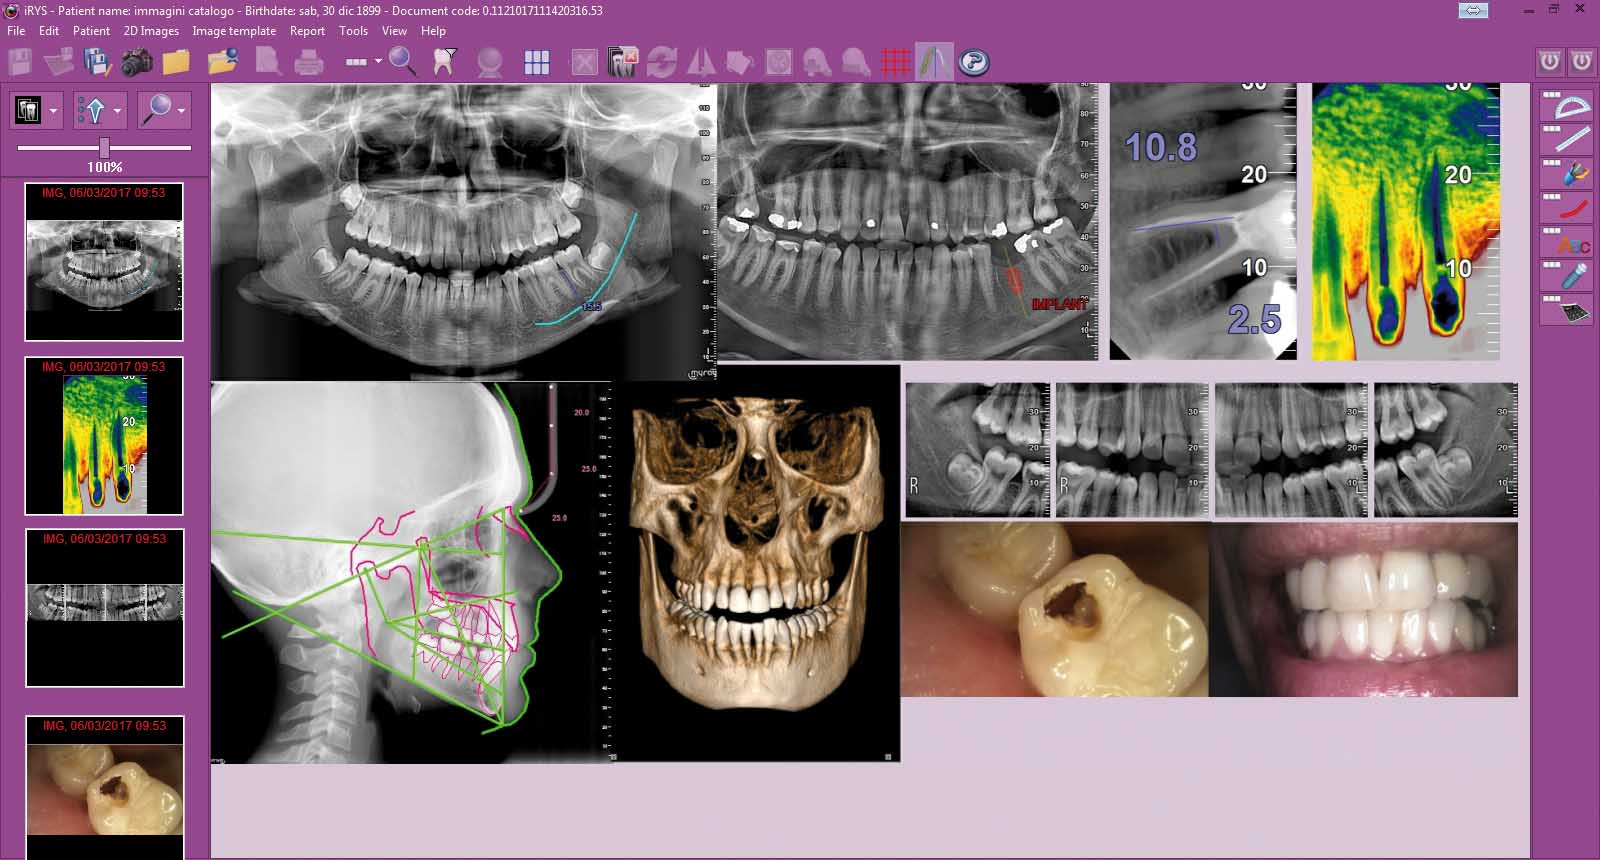

Moderný RTG je prirodzenou súčasťou digitálneho workflow. Snímky sú dostupné v priebehu pár sekúnd, jednoducho archivovateľné a okamžite použiteľné pri komunikácii s pacientom či laboratóriom. Pri kombinácii s digitálnymi senzormi alebo so softvérom typu iRYS získavate rýchly prehľad, lepšiu dokumentáciu a väčšiu dôveru pacienta, ktorý vidí a rozumie tomu, čo riešite.